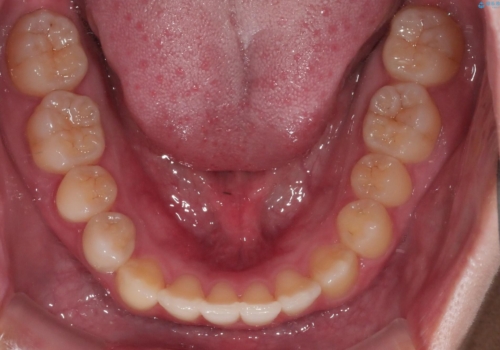

マイクロインプラントを使用することで非抜歯での治療が可能となりました。

マイクロインプラントを使用せずに無理に非抜歯治療を行った場合、

治療後に出っ歯になってしまうなどの問題が起きる可能性が高いです。